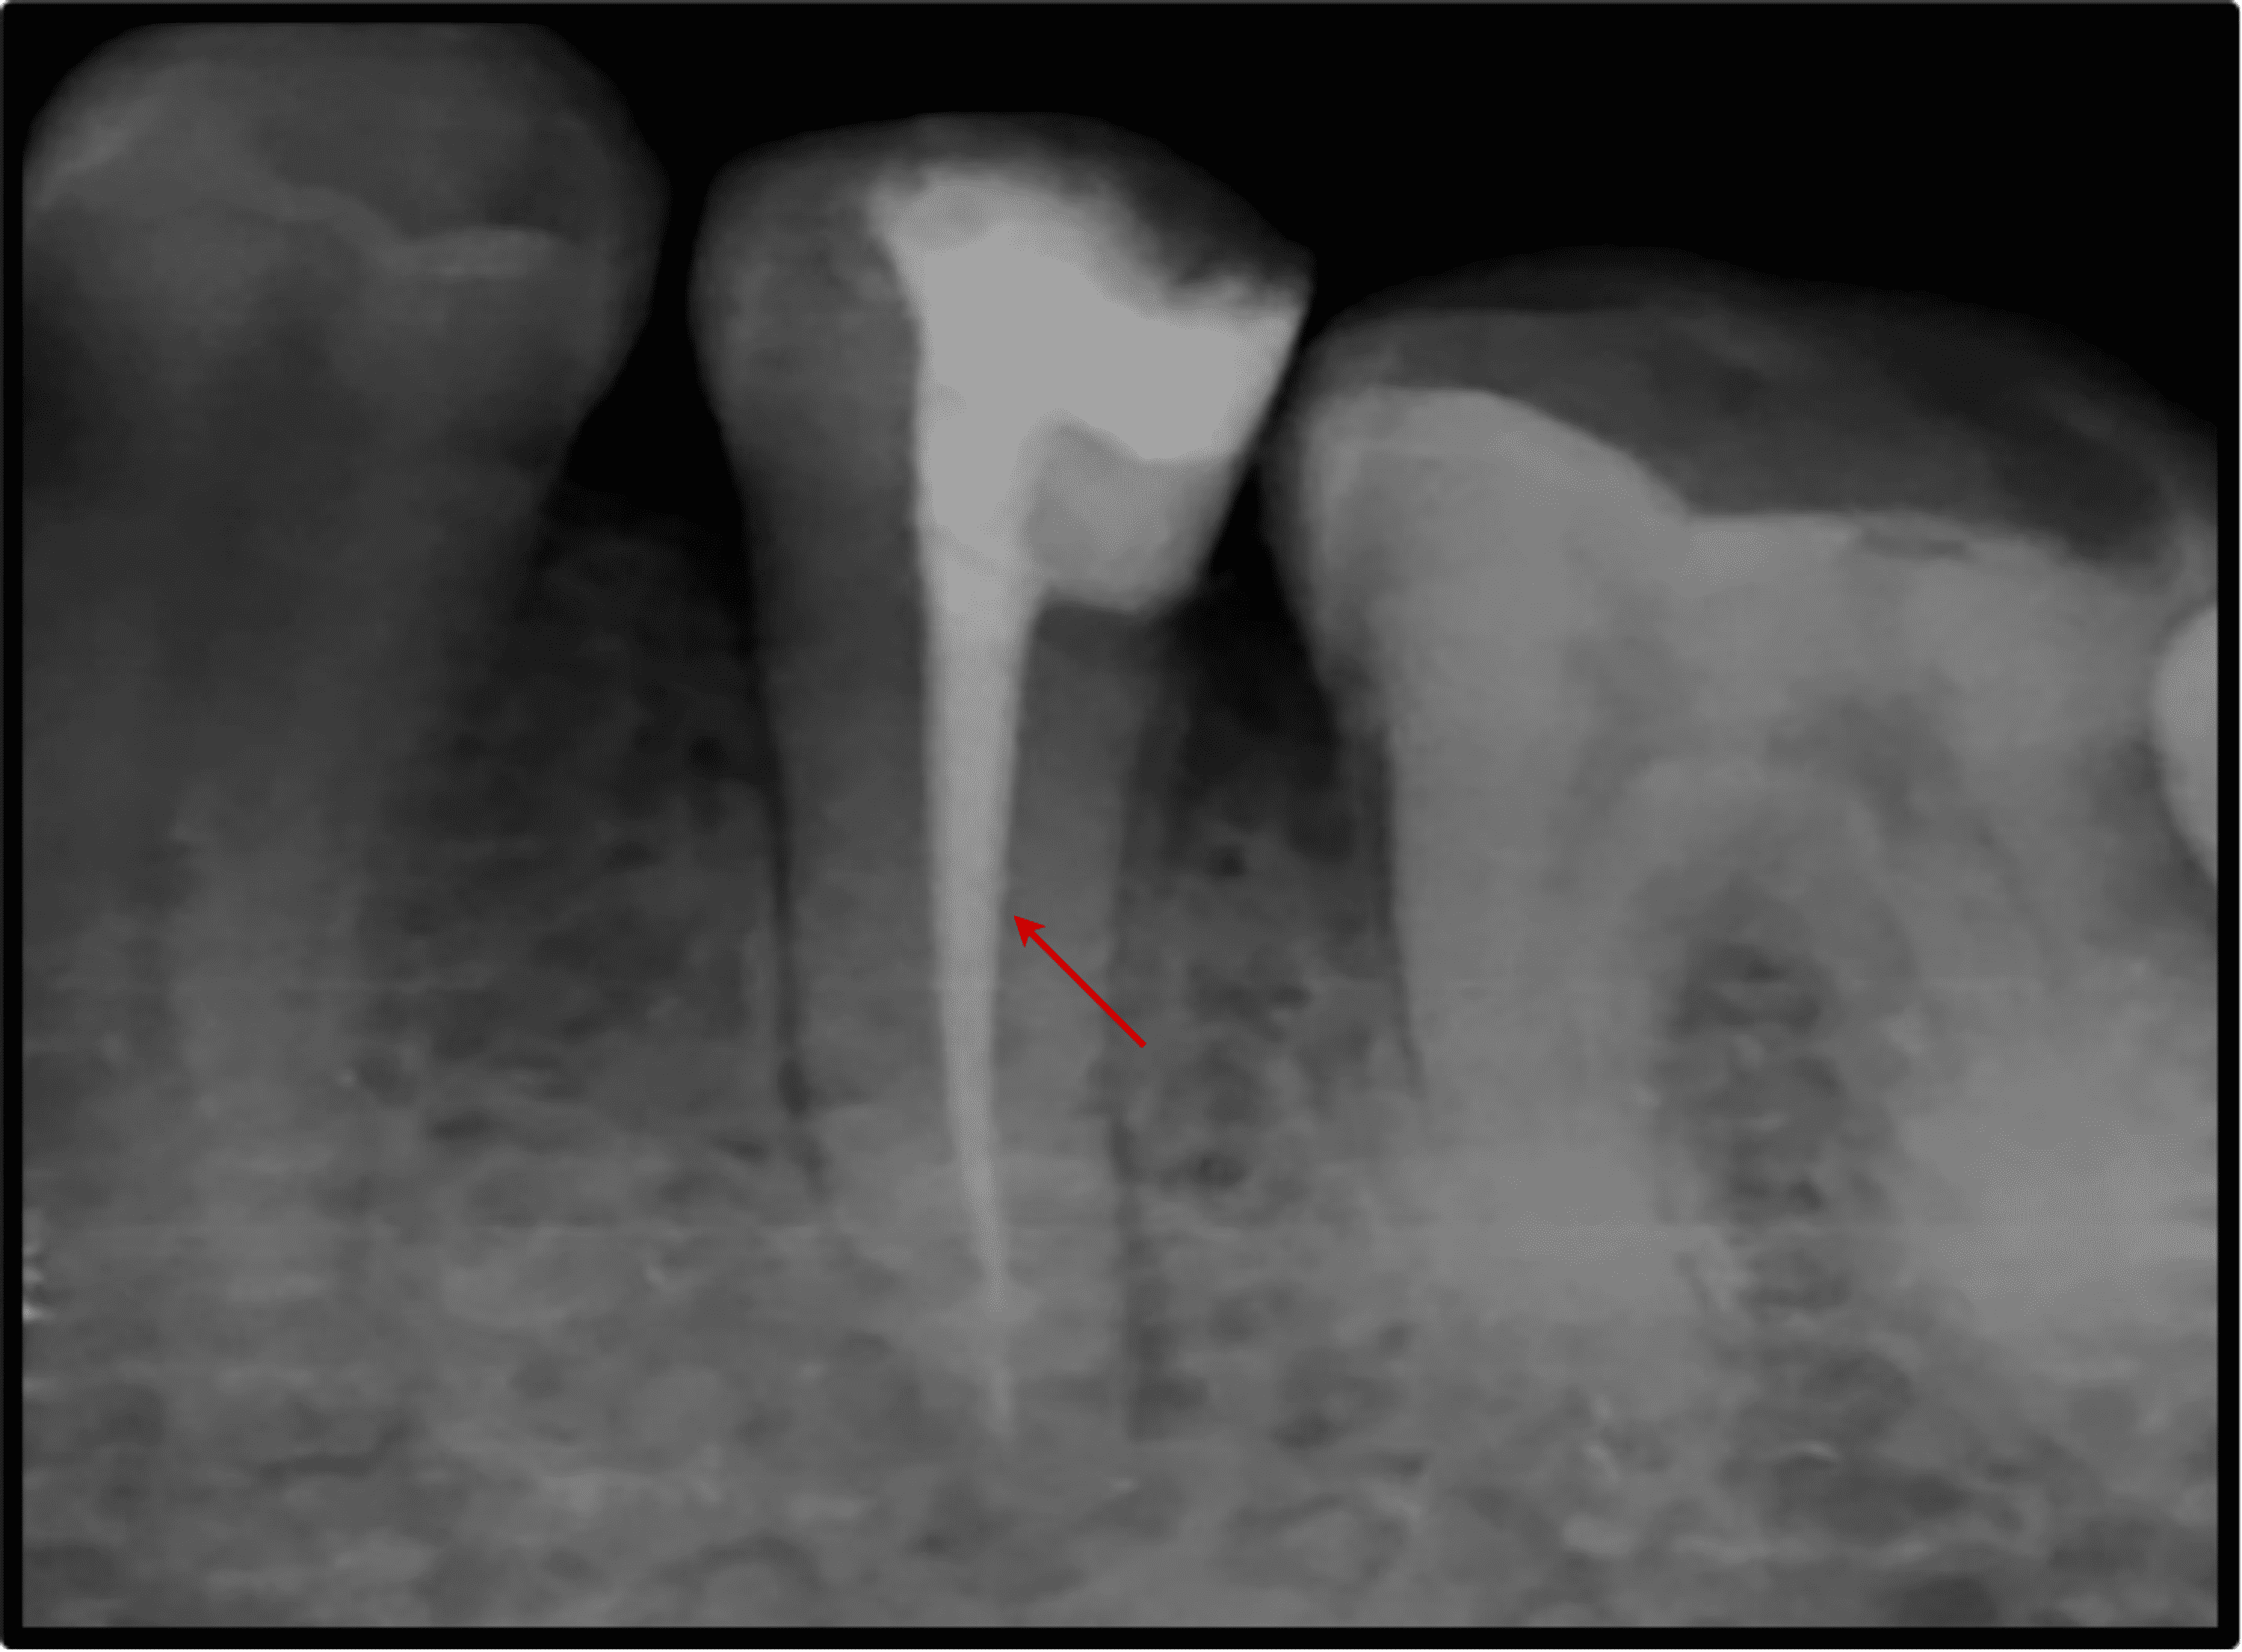

Vertical root fracture diagnosis of crowned premolars with root canal Root Canal Xray Premolar The aims of this case presentation are to report a unique case of root canal treatment involving five root canals in the mandibular first. Various methods are employed to evaluate the root and canal morphology of the mandibular first premolars. The aim of this case was to understand and treat the intricate root canal anatomy observed in complex maxillary. The. Root Canal Xray Premolar.

Figure 7. Radiographic appearance following root canal treatment Root Canal Xray Premolar Various methods are employed to evaluate the root and canal morphology of the mandibular first premolars. The aims of this case presentation are to report a unique case of root canal treatment involving five root canals in the mandibular first. The aim of this case was to understand and treat the intricate root canal anatomy observed in complex maxillary. The. Root Canal Xray Premolar.